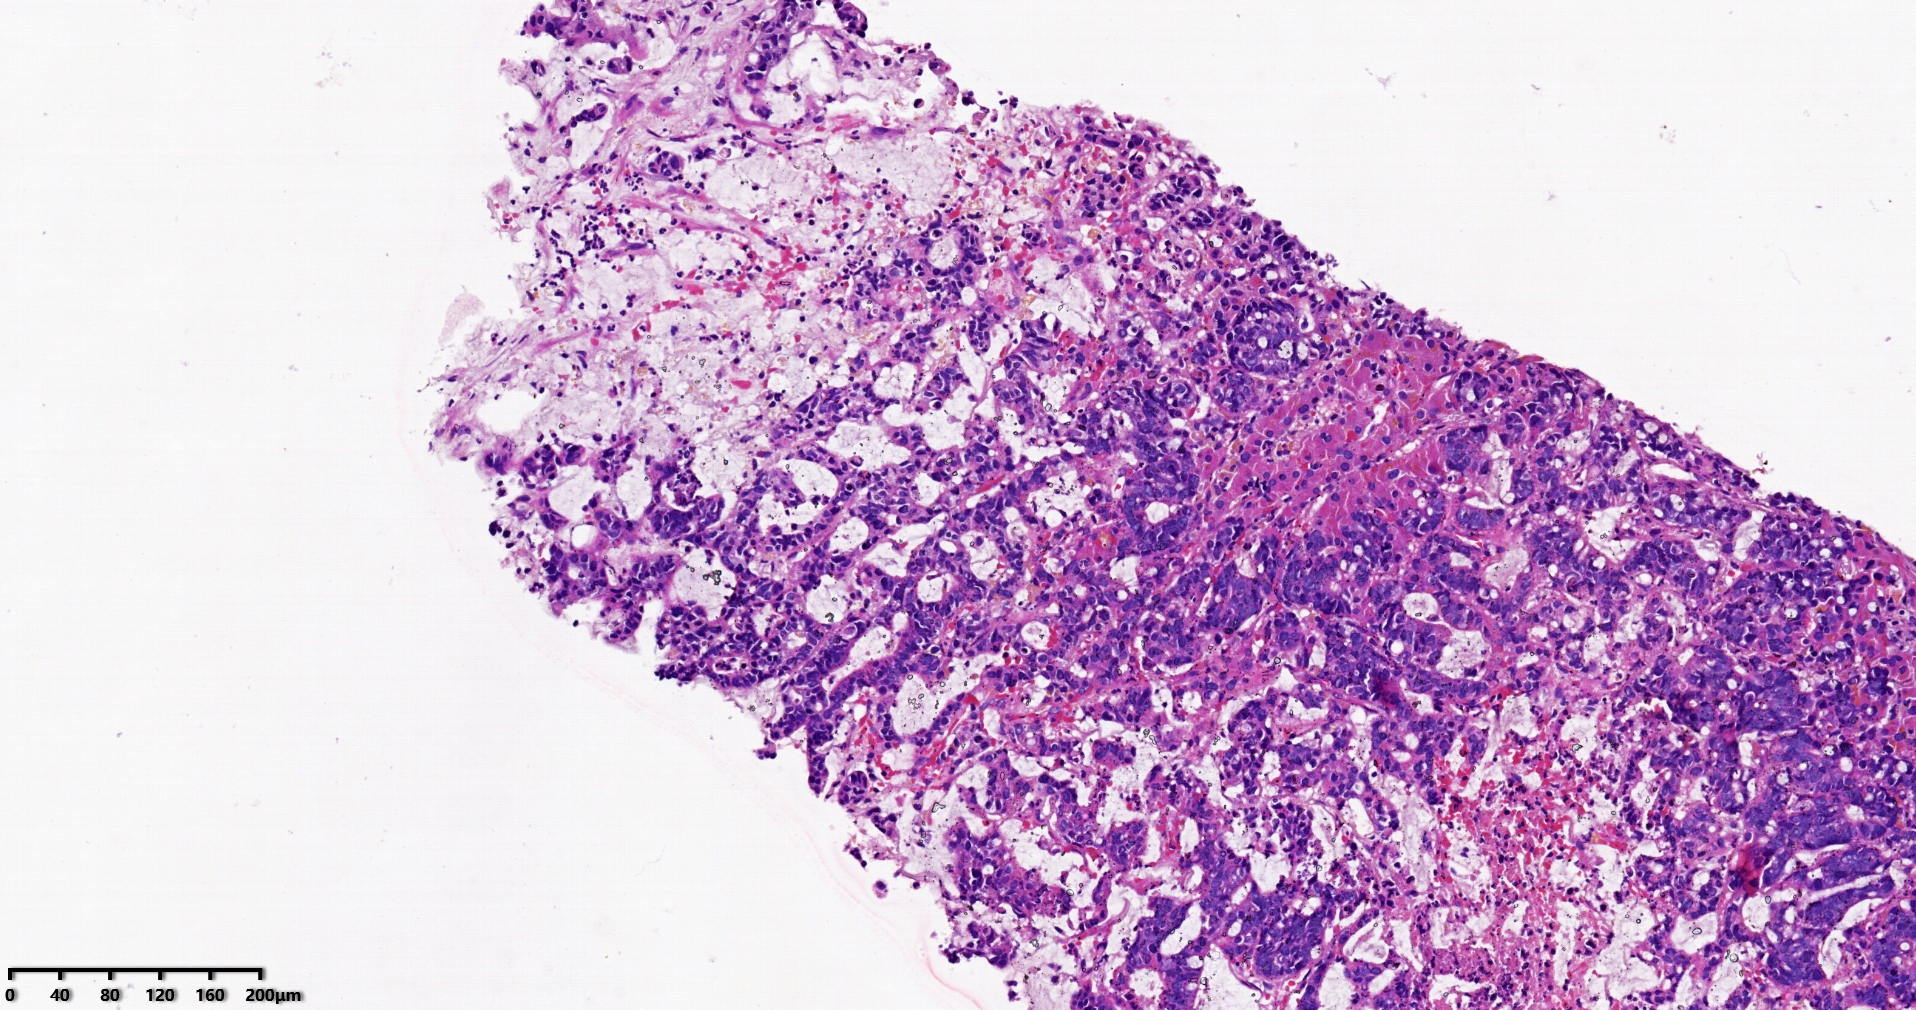

标本名称肝脏穿刺

大体所见灰白灰红色穿刺活检组织两条,长1.7-1.9cm,直径0.1-0.2cm。

考虑符合:肝内胆管癌

考虑转移性黏液腺癌,消化道来源可能,建议做免疫组化,排除胆管源性。